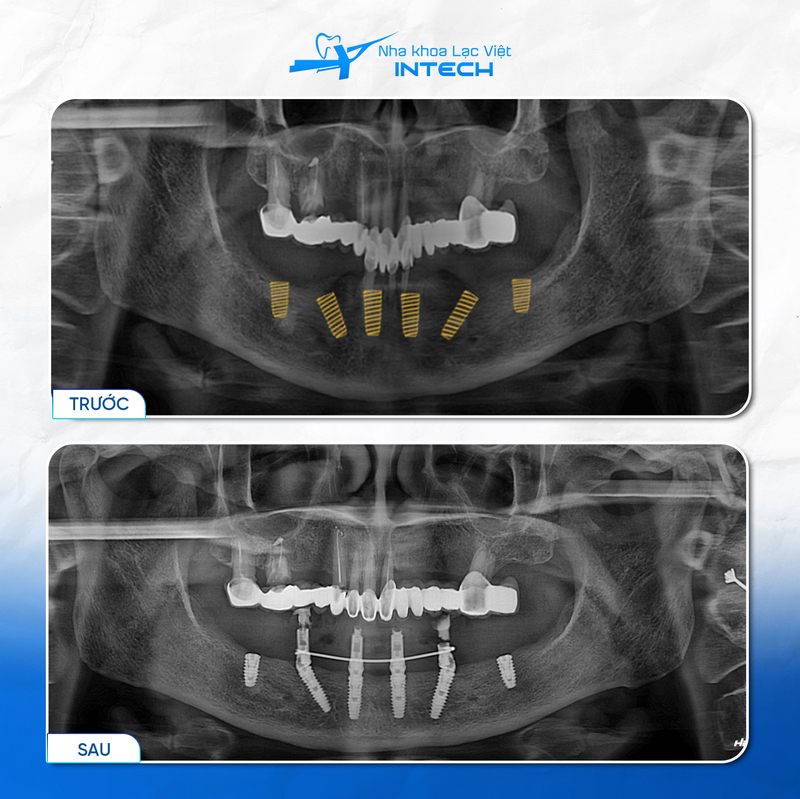

Cấy ghép implant là phương pháp thay thế răng đã mất bằng cách cấy trực tiếp một trụ răng nhân tạo (Implant Fixture) vào xương hàm để làm chân răng mới, phương pháp trồng răng Implant đang trở thành một giải pháp hiệu quả hàng đầu cho những người mất răng, nhờ vào những lợi ích mà nó mang lại so với các phương pháp truyền thống như cầu răng sứ và hàm giả tháo lắp. Trong đó, 6 lợi ích vượt trội của cắm Implant hơn cả mà bác sĩ Nguyễn Gia Bảo đề cập gồm:

Với cơ chế cấy ghép Implant, trụ Titanium gắn vào xương hàm giúp truyền lực nhai trực tiếp xuống xương, kích thích sự phát triển của xương và ngăn ngừa quá trình tiêu xương. Lợi ích của cấy ghép Implant giúp duy trì cấu trúc khuôn mặt, bảo vệ sức khỏe hàm răng và ngăn chặn sự suy yếu của xương hàm, qua đó đảm bảo vẻ đẹp và chức năng lâu dài của răng miệng.